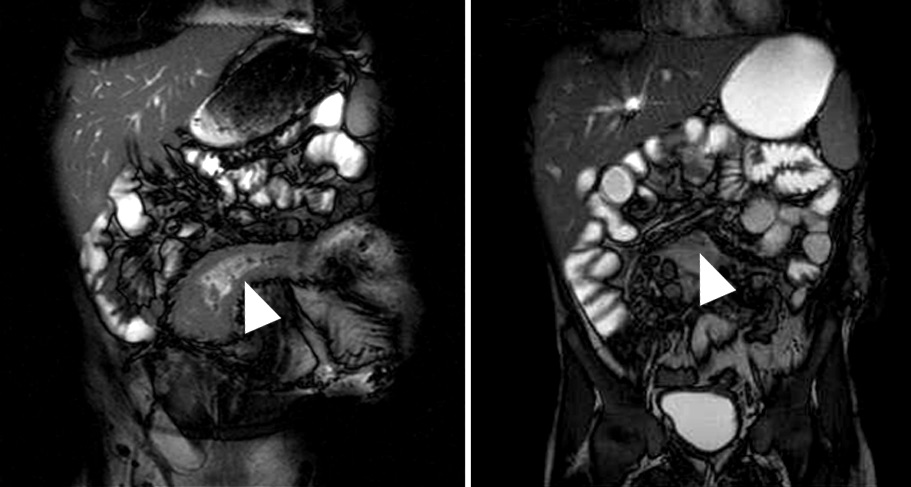

Figura 5

Enfermedad de Crohn

a y b) Secuencias T2 con saturación grasa en el

plano axial. Engrosamiento parietal circunferencial

de la última asa ileal sin edema que contacta con

el colon transverso presentando adherencias con

el mismo (flecha). Tracto sinusal que se extiende

desde el asa alterada al borde anterior del músculo

ilíaco derecho (flecha corta).

c) Secuencia T1 con

saturación grasa y gadolinio, pequeña colección

líquida en el espesor muscular con realce parietal

(punta de flecha)